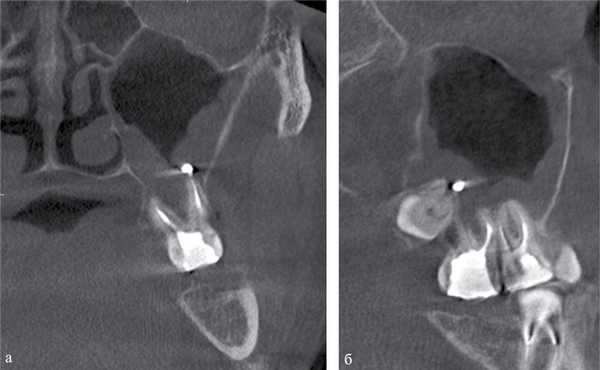

Пломбировочный материал был обнаружен у 38 (22,8%) пациентов (рис. 2). Из них у 34 (20,4%) больных в подслизистом слое нижней стенки синуса, у 4 (2,4%) — в верхнем отделе у медиальной стенки синуса (рис. 3). У 8 (4,8%) пациентов диагностированы ошибки стоматологической имплантации: верхушка импланта была погружена в полость синуса, что стало причиной развития хронического одонтогенного верхнечелюстного синусита, а также осложнений в виде хронического полисинусита (n=4; 2,4%).

Рис. 2. МСКТ. Коронарная (а) и сагиттальная (б) реконструкции правого верхнечелюстного синуса пациента К., 29 лет. Диагноз: правосторонний одонтогенный хронический верхнечелюстной синусит. Корни зубов 1.6, 1.7 и 1.8 погружены в полость верхнечелюстного синуса. Состояние после эндодонтического лечения зубов 1.6 и 1.7, с выведением пломбировочного материала за верхушку небного корня 1.7. В области корней зубов 1.6 и 1.7 отмечается разрежение костной ткани с нечеткими неровными контурами (рентгенологические признаки гранулирующего периодонтита). В нижнем отделе синуса определяется пристеночное мягкотканное образование с полицикличным контуром, костные стенки синуса в данной области не прослеживаются.

Рис. 3. КЛКТ. Сагиттальная реконструкция, правый верхнечелюстной синус. Пациент У., 48 лет. Диагноз: правосторонний одонтогенный хронический верхнечелюстной синусит. Зубы 1.6 и 1.7 после эндодонтического лечения, отмечается выведение пломбировочного материала за верхушки корней зуба 1.6 (материал располагается в костной ткани альвеолярного отростка и в подслизистом слое синуса). Определяется разрежение костной ткани в области корней 1.6 и 1.7, костная стенка синуса в данной области не прослеживается (стрелка). В нижнем отделе синуса определяется утолщение слизистой оболочки до 10 мм, в верхнемедиальном отделе синуса визуализируется инородное тело неправильной формы металлической плотности (соответствует фрагментам пломбировочного материала).